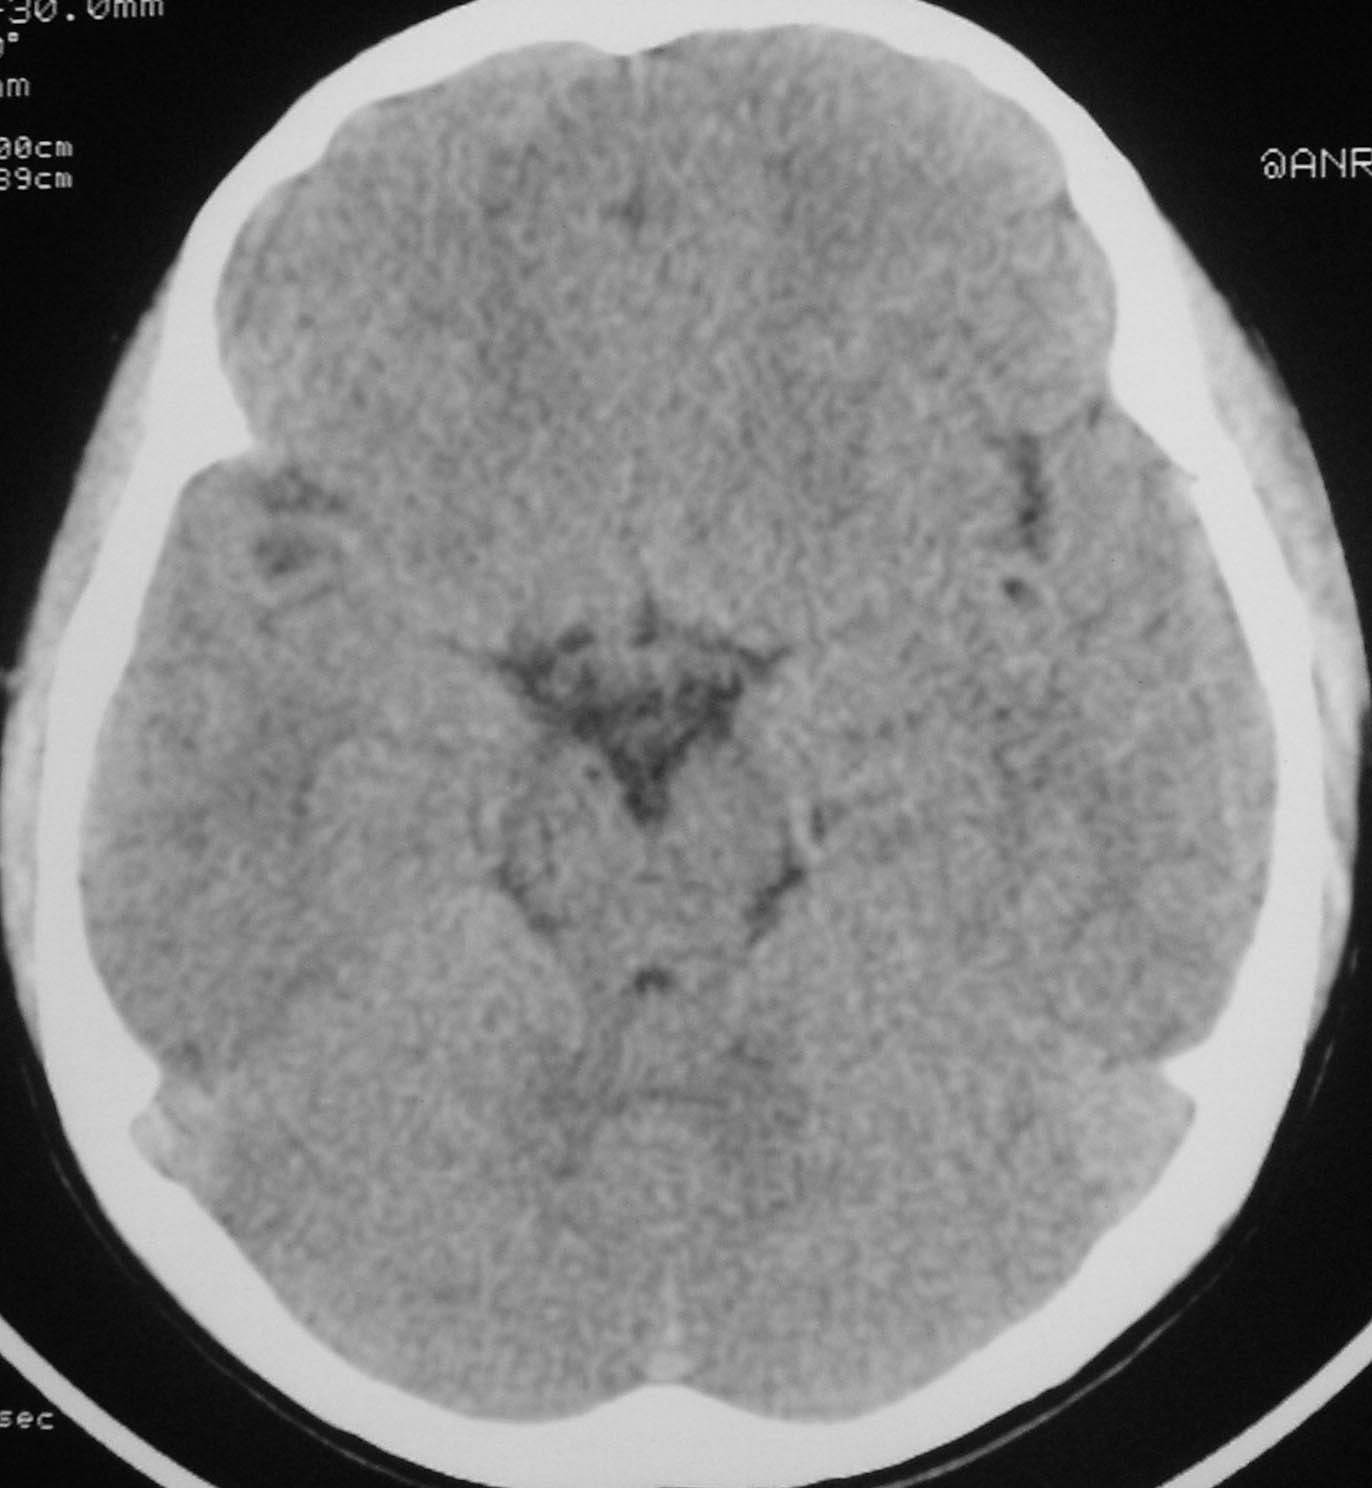

以下是引用余辉在2007-4-28 19:55:00的发言:[br]血管畸形?增强一下

以下是引用jw-830在2007-4-28 20:22:00的发言:[br]考虑血管畸形可能建议增强

以下是引用ysxyy在2007-4-29 21:14:00的发言:[br]像是假像,如果不放心可以偿试一下:[br]你用听眦线为基线扫一下,再用听眶线扫一下,就是说用不同的角度扫同一个地方;[br]看看有无变化,是不是有相同或相似的表现,即可鉴别;